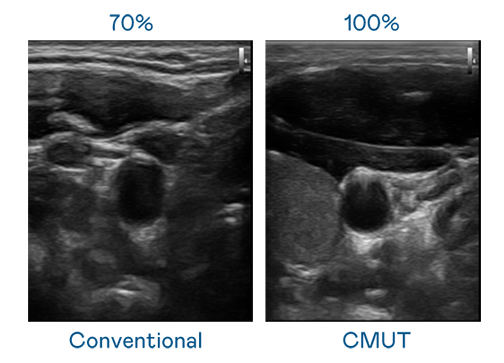

CMUT 技术是一种用电容式微机电元件来产生超音波讯号的技术。与传统 PZT 压电式技术相比,CMUT 频宽增加 30%,更宽频的超音波讯号让影像解析度大幅提升,是实现高影像品质医疗超音波扫描、促进精准医疗发展的关键技术。

大频宽带来超清晰影像

超音波影像的解析度高低,首先取决于探头能发出的讯号频宽。5001拉斯维加斯 CMUT 可提供高清晰的超音波讯号,提供高频宽、高灵敏度、影像纹理细节更高的超音波影像,协助医护人员缩短影像判读时间及利用精准的医疗影像进行诊断。